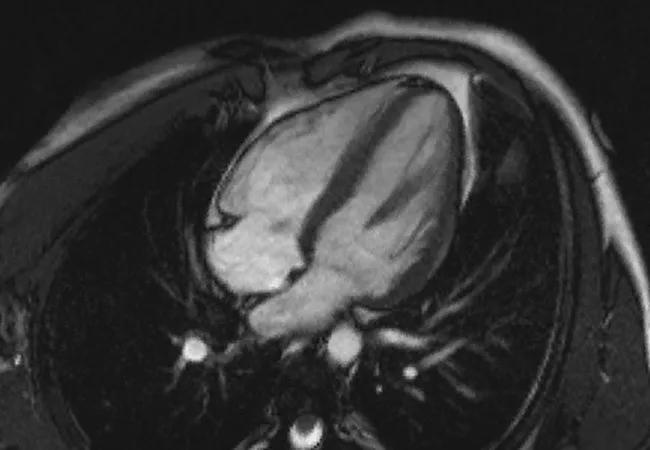

Imaging Options Compared for Septal and Mitral Measurement in Myectomy for HOCM

heart affected by hypertrophic cardiomyopathy

For patients with hypertrophic obstructive cardiomyopathy (HOCM), optimal surgical planning to relieve left ventricular outflow tract obstruction (LVOTO) during surgical myectomy demands precise morphological assessment. However, data on concurrence between various types of multimodality imaging to provide such assessment are scarce. Now Cleveland Clinic researchers have published prospective data on this question, outlining which measurements are best for specific purposes.